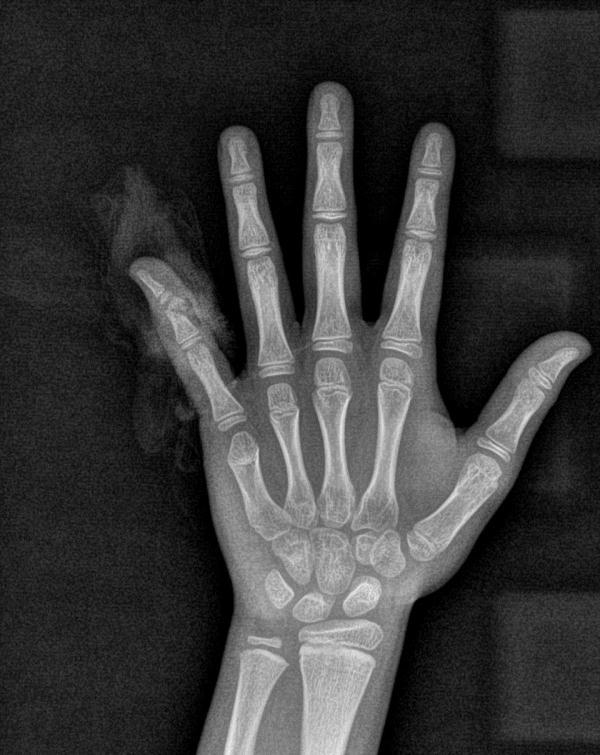

△X线检查结果显示手指离断伤